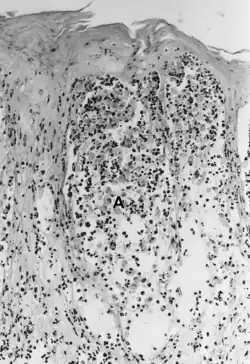

The histopathology of FMD, SVD, and VES is considered quite similar. The lesions begin in the stratum spinosum, where vesicles form because of hydropic degeneration and intercellular edema. Keratinocytes die, become spherical, and float as single or clustered cells in the vesicular fluid (spongiosa) (Fig. 25.5A). The stratum basale essentially remains intact but may be somewhat disrupted by VESV infection (Mebus 1977).

The histopathology of VS in cattle has been carefully studied by Seibold and Sharp (1960) and described by Jubb et al. (1985) and is probably equivalent for swine. The lesions develop in the stratum spinosum with intercellular edema that stretches the intercellular bridges (desmosomes). Cells remain attached at the ends parallel to the stratum basale but are separated lengthwise by intercellular edema, giving a reticular or “Japanese lantern” appearance (Fig. 25.5B). Cells become necrotic in the later stages of the lesion. The epithelial layers above the stratum basale separate in about 30% of the cases. Loss of vesicular fluid through the stratum corneum occurs frequently, and vesicles may not be observed.